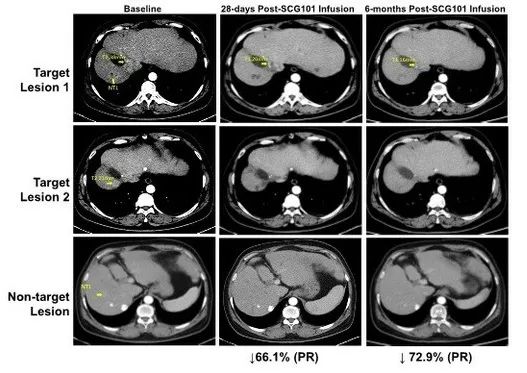

本次临床研究,选取了一例患有乙型肝炎病毒(HBV)相关肝细胞癌(HCC)的患者,在试验期间,仅给予单剂SCG101输注,未接受其他抗肿瘤治疗,结果显示:

1、肿瘤缓解:在治疗第28天,患者肿瘤靶病灶相比基线缩小66%,达到部分缓解(PR),并在第4个月进一步缩小74.5%;另一处病灶则完全消失。数据截止时,该患者保持持续缓解状态,肿瘤未进展时间已>6.9个月。

图2 HBV相关肝细胞癌患者SCG101回输前后影像学变化

▲图源“CISION”,版权归原作者所有,如无意中侵犯了知识产权,请联系我们删除